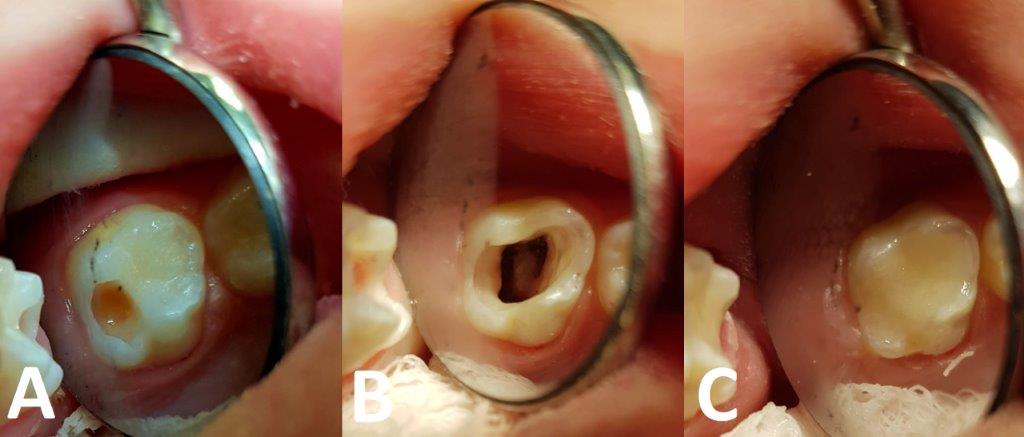

Rycina 1 prezentuje poszczególne etapy amputacji z użyciem siarczanu żelaza, a ryc. 2 to zdjęcia wykonane u 2,5-letniej pacjentki w trakcie zabiegu amputacji miazgi z zastosowaniem preparatu zawierającego w swoim składzie siarczan żelaza (20% siarczan żelaza, Pulpogel, Chema-Elektromet).

Ryc. 1. Ząb z próchnicą głęboką powikłaną. A. Próchnica penetruje do miazgi, niszcząc sklepienie komory zęba; B. Stan po całkowitym opracowaniu ubytku, zdjęciu sklepienia komory i odcięciu miazgi na wysokości ujść kanałów; widoczne krwawienie z kikutów miazgi pozostawionych w obrębie kanałów; C. Wcieranie w krwawiącą miazgę preparatu zawierającego siarczan żelaza; D. Wypłukanie sprayem wodno-powietrznym brunatnych skrzepów powstałych w wyniku reakcji żelu z krwią; E. Stan po przykryciu miazgi kanałowej cementem tlenkowo-cynkowo-eugenolowym, założeniu podkładu oraz odbudowie korony materiałem plastycznym.